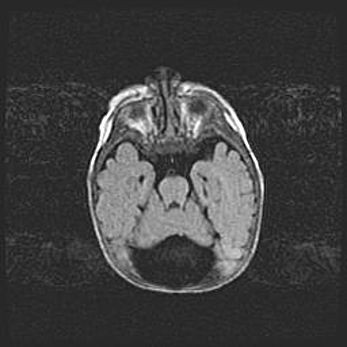

Лейкомаляция с кистозно-глиозной дегенерацией головного мозга.

Возраст: 2 месяца 25 дней

Вес: 6400 г

Окружность головы: 40 см

Срок гестации: 41 неделя

Лейкомаляцию относят к ишемически-гипоксическим повреждениям головного мозга, диагностируемым у новорожденных. При лейкомаляции в головном мозге обнаруживают очаги некроза, возникшие после тяжелой гипоксии и нарушения кровотока. В процессе морфогенеза очаги проходят три стадии: 1) развития некроза, 2) резорбции и 3) формирования глиозного рубца или кисты. Перивентрикулярная лейкомаляция (ПЛ) встречается примерно в 12% случаев среди новорожденных, обычно – у недоношенных детей, причем, частота ее зависит от массы, с которой младенец появился на свет. Наибольшее число малышей страдает лейкомаляцией, если масса при рождении 1500-2500 г.